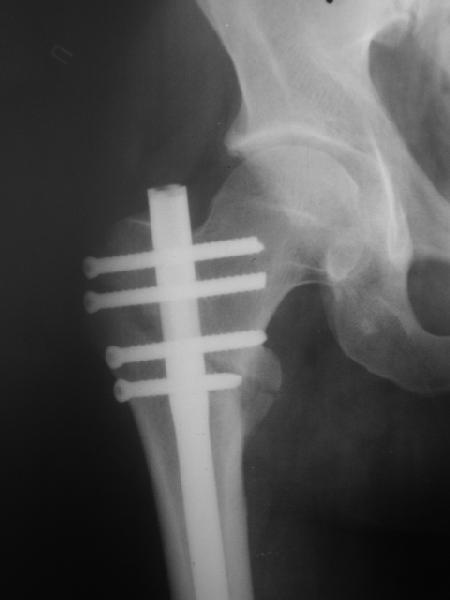

При межвертельных переломах с цефаломедуллярными гвоздями бывает, что проксимальый винт проходит или черед периферический отломок, или прямо над ним. И если остался диастаз, то этот винт при осевой нагрузке не дает сблизиться отломкам. Пример такого остеосинтеза в застарелом случае в приложении.

В качестве предупреждающей меры можно долотом разрушить латеральную стенку дистального отломка под винтом.